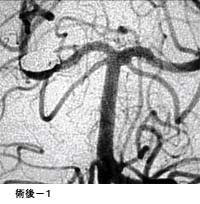

破裂脳動脈瘤に対するGDC(コイル)塞栓術

術後 コイルにより動脈瘤が写らなくなりました。